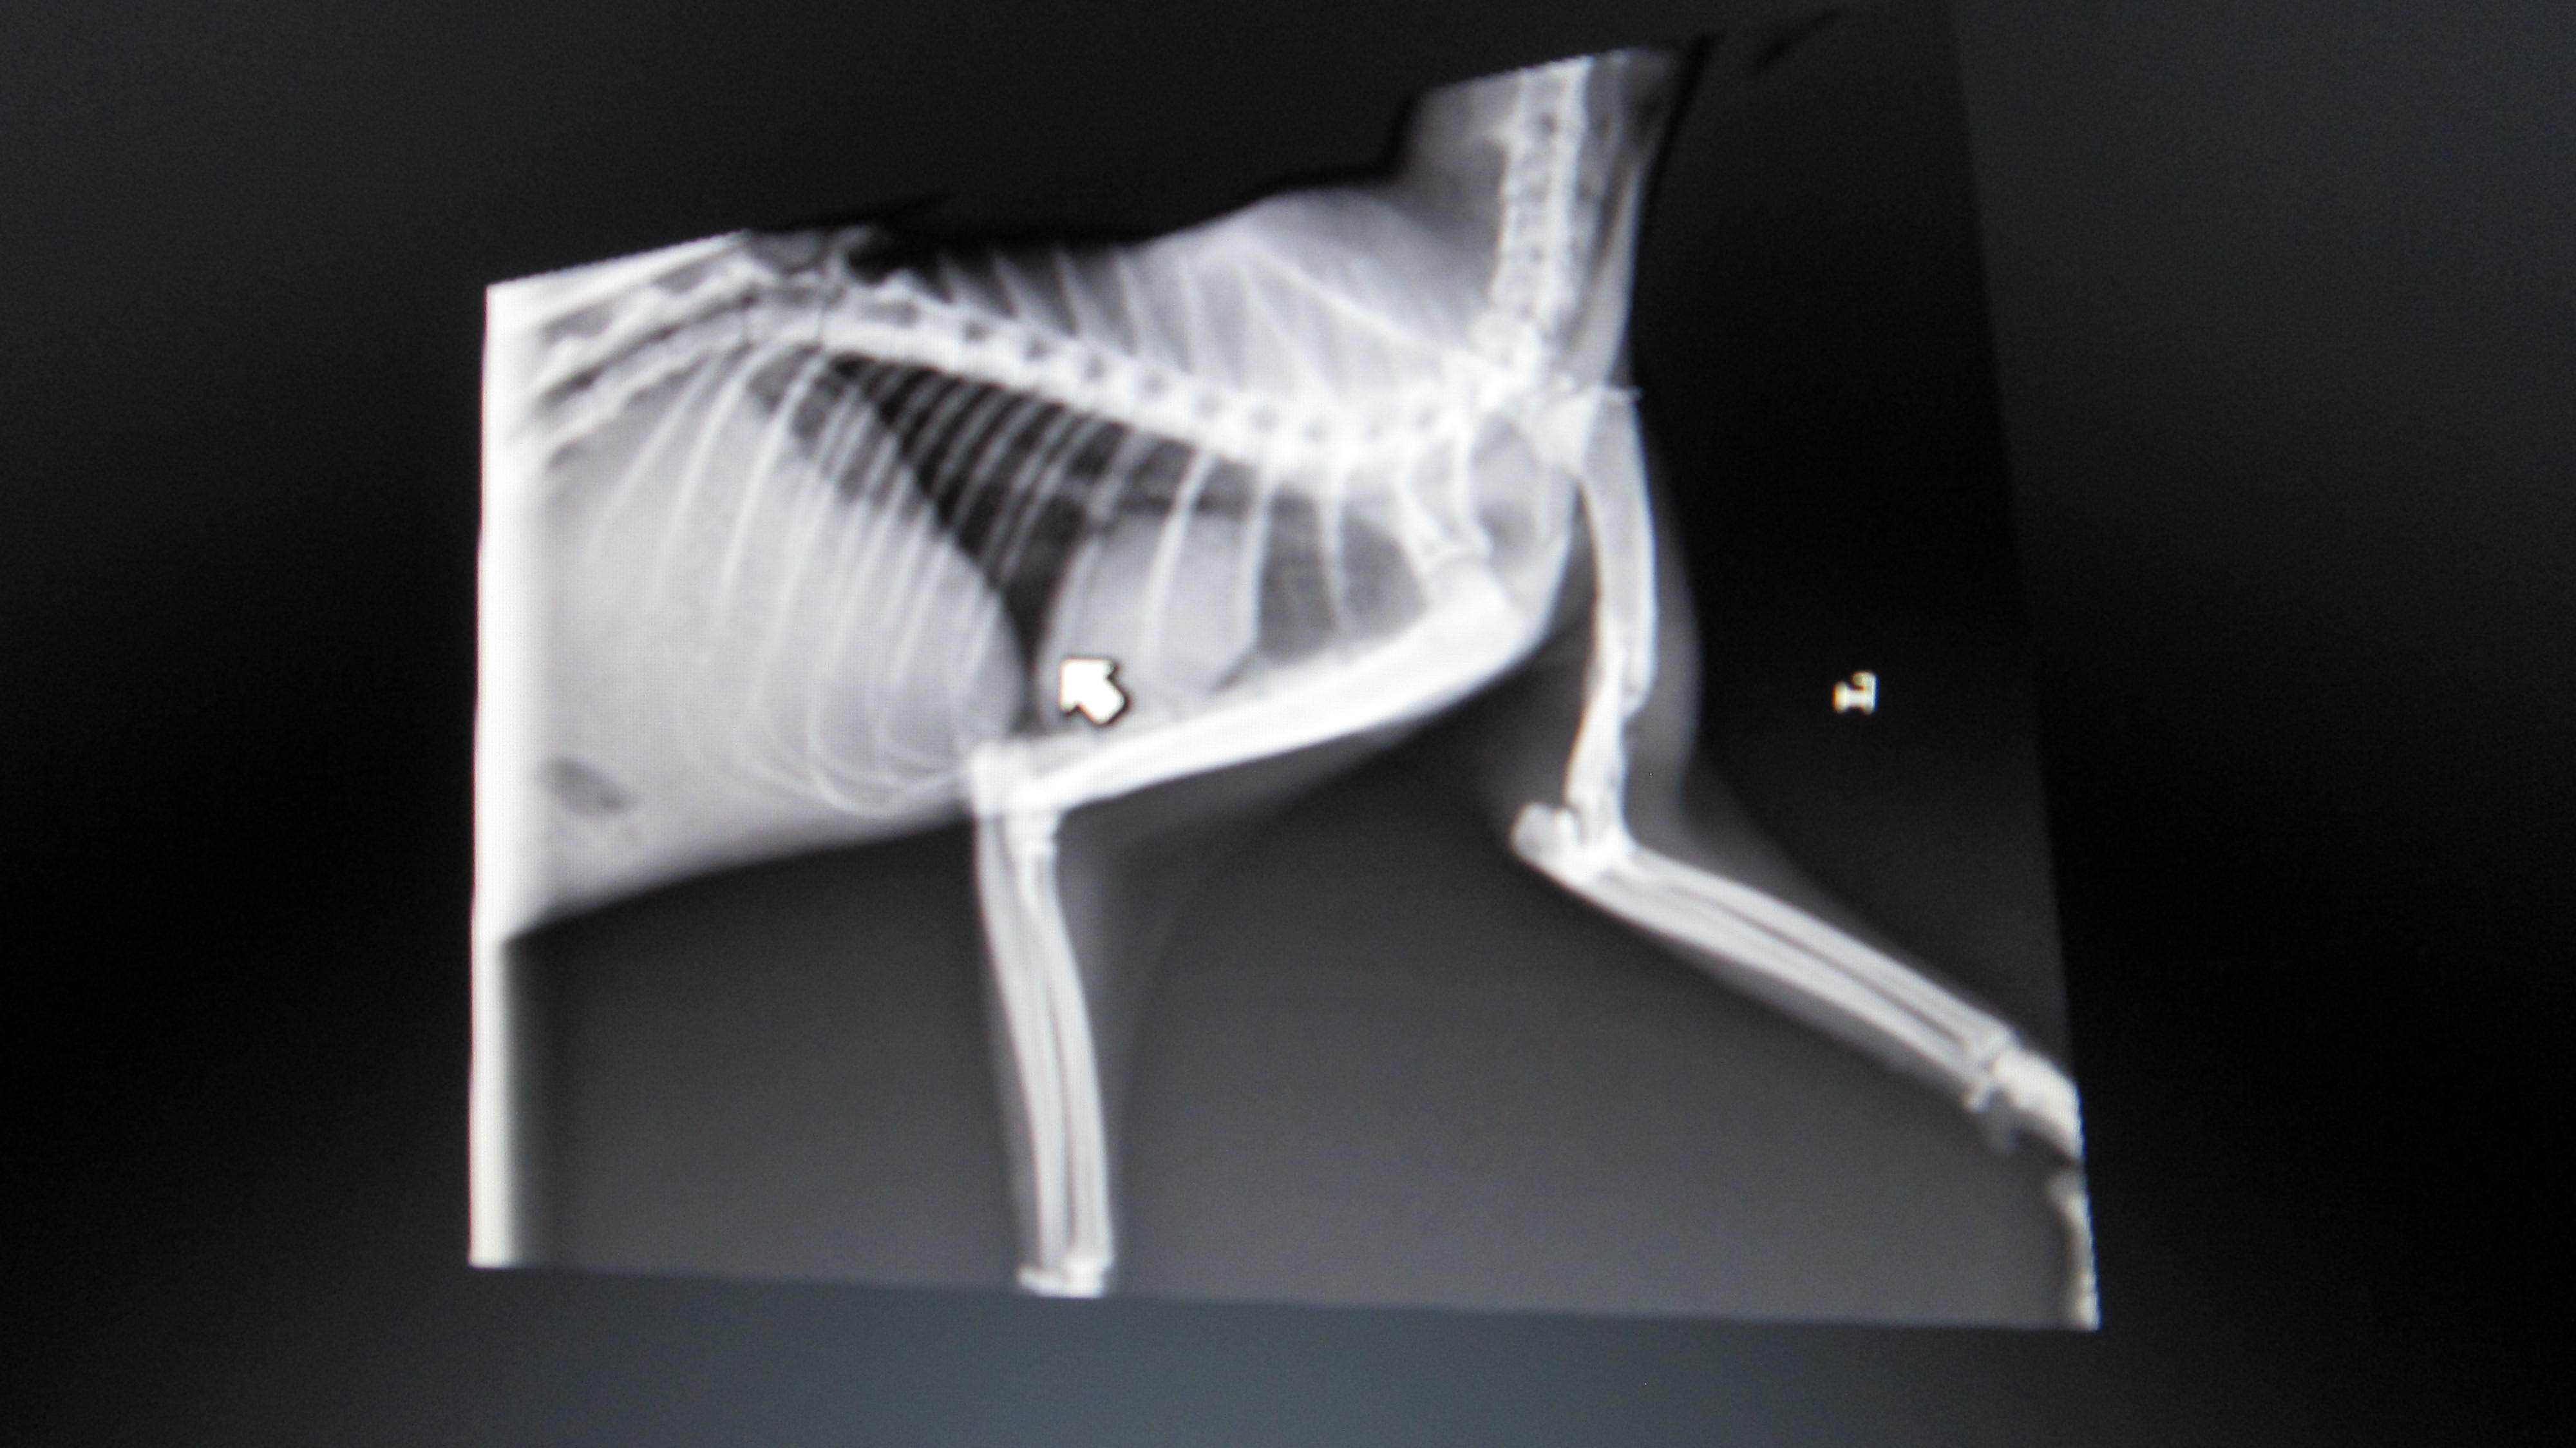

主題: 八德市大湳市場倒在路旁的斷腿貓 (第二次醫助通報) 申請者姓名: 李明明 花色: 申請日期: 2013-06-09 22:30:55 申請者部落格: 申請者臉書網址: 所在縣市/合作醫院: 台北市/長青動物醫院 治療費用: 27160元 需求人數: 29人 已結案 (2013-08-06 14:00:31) 報名人員: 白婷(已付款)、Forest(已付款)、Alison Lee(已付款)、euca(已付款)、言則(已付款)、miraai(已付款)、周小蕾(已付款)、sfeng(已付款)、vivian(已付款)、Rachel Chen x2(已付款)、宋小璉 x2(已付款)、chiawei(已付款)、suxiwen(已付款)、Ping Hussard(已付款)、PS Yeh x2(已付款)、Vinnie Hsu(已付款)、Iris Hsu、Iris Hsu(已付款)、nicole chen(已付款)、Sunny Chen、Sunny Chen(已付款)、蘇小優(已付款)、林嘉南(已付款)、Nonie Huang(已付款)、Ariel Yu-Ting Tu、Kyra Chu(已付款)、林艾蓁(已付款)、chiawei(已付款)、JASON(已付款)、 候補人員: 動物病情說明: 5/11白蛋白已由1.9上升至2.3,食慾佳;每天仍須早晚兩次左後腳背傷口清創,並配合抗生素治療,促進傷口癒合,醫院將視傷口癒合情形調整清創次數。腹水部分先以補充營養與熱量,觀察白蛋白指數回升情形,決定後續治療。另,醫生告知,觀察馬太昨天 (5/12) 有癲癇發作一次,目前繼續觀察中。左前肢雖骨折但已能稍微站立,恢復情形較佳;後肢因關節韌帶受損、腳背傷口清創&肌肉腫脹,恢復較緩慢。 動物近況說明: 斷腿貓(馬太) 6/2 出院,醫療費用合計27,160元 , 已帶回桃園就近照顧,限制活動並定時每日傷口換藥,穩定復原中。